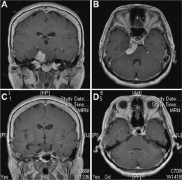

脑膜瘤放疗后并发胶质瘤病例。患者,女,45岁,2011年因间歇性头痛、恶心呕吐,考虑脑膜瘤(图1A、1B)进行头颅MRI检查,然后进行手术治疗,术后病理显示...